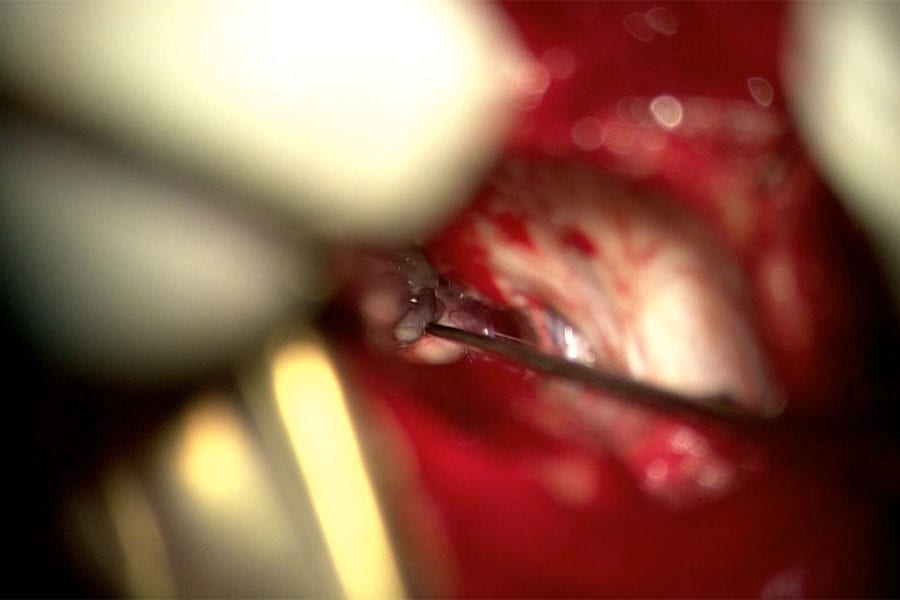

This patient with Trigeminal Neuralgia had surgery in 2012 by another surgeon at another institution. Initially, she felt well, but the pain gradually returned over…